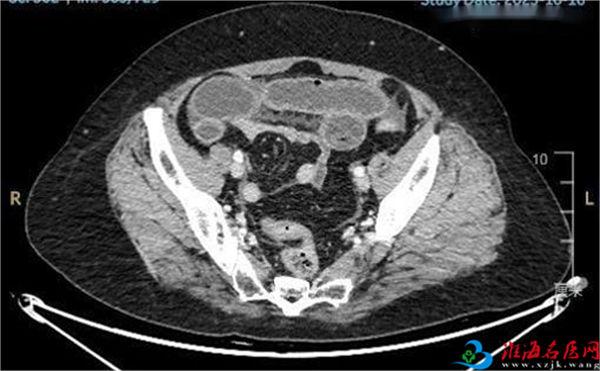

吃完当天李阿姨就肚子疼,去社区医院打水,连续打六天肚子还是疼,直到腹痛难忍才急忙赶到徐州医科大学附属医院急诊就诊。通过腹部CT发现多发小肠胀气、积液,可见气液平,提示小肠梗阻表现,腹盆腔积液。当日胃肠外科值班医生孟松主任结合病史,查体和CT检查,判断李阿姨得了小肠梗阻,且经过了积极的保守治疗后腹痛腹胀依旧不见好转,李阿姨辗转反侧不能停歇,遂建议李阿姨紧急手术探查。

手术中,末端小肠扪及一枚较大的粪石卡在小肠,导致小肠不通,近端小肠扩张积液明显,可扪及多个较小的粪石。孟松主任从李阿姨的小肠中取出5块粪石,其中最大一块近5公分,最小的也有2公分。术后李阿姨腹痛腹胀明显缓解,顺利出院。为了避免此类事件再次发生,李阿姨想通过自己的案例告诉大家:千万不要把冬枣和山楂一起吃,真的是太痛苦了,花钱受罪。